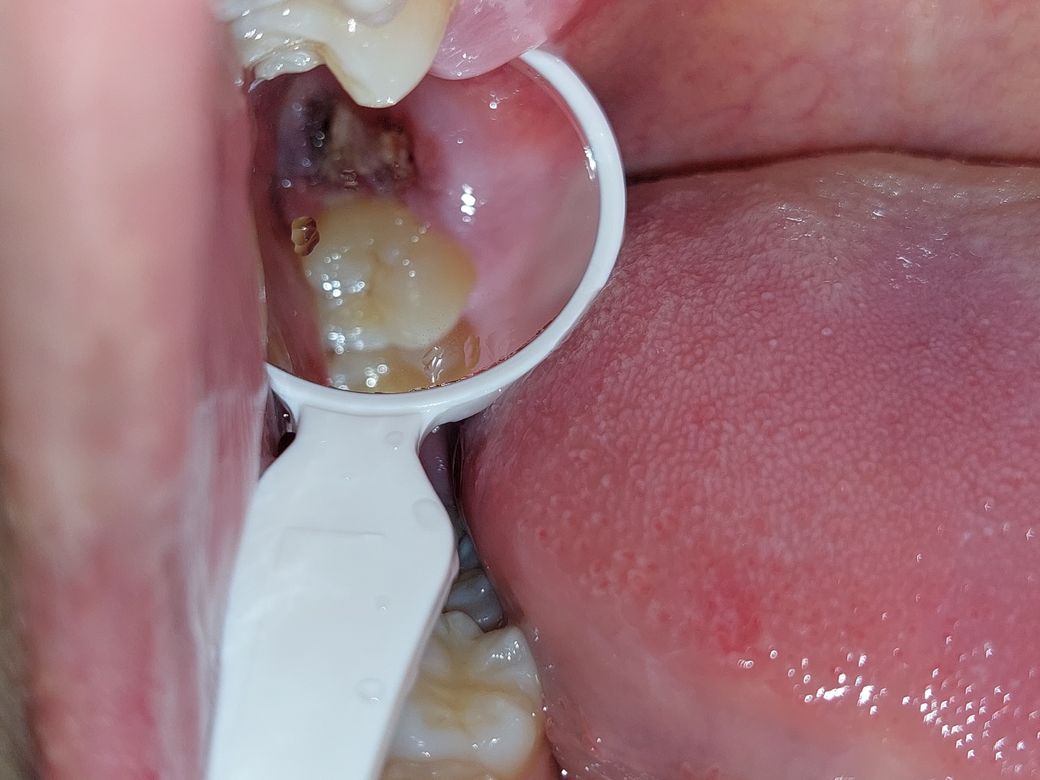

안녕하세요. 오늘 사랑니 발치하고 3시간 정도 있다 발치한 곳을 확인해 보았더니, 안에 하얀 덩어리들이 있는 것을 보았습니다. 뽑는 과정에서 사랑니를 돌려서 뽑은 듯한 느낌이 들었어서 혹시나 사랑니 뿌리가 남은 것이 아닐까 걱정이 되어 질문 드립니다.

아래는 제가 찍은 사진입니다.

사진상으로는 정확히 알수가 없고 엑스레이 사진을 찍어보면 뿌리가 남은건지 제대로 알수 잇습니다. 하얗게 보이는건 발치를 하고 나서 그쪽부위에 치유되는과정중에 생기는거니 크게 걱정은안하셔도 됩니다.

혈병이 보이는것일수도 있고, 지혈제를 넣은것일수도 있습니다.

직접봐야 알 수 있겠지만 치아뿌리가 남아있는 것으로는 보이지 않고 사진상으로는 상피세포가 회복을 위해 생기고 있는 것으로 보입니다.